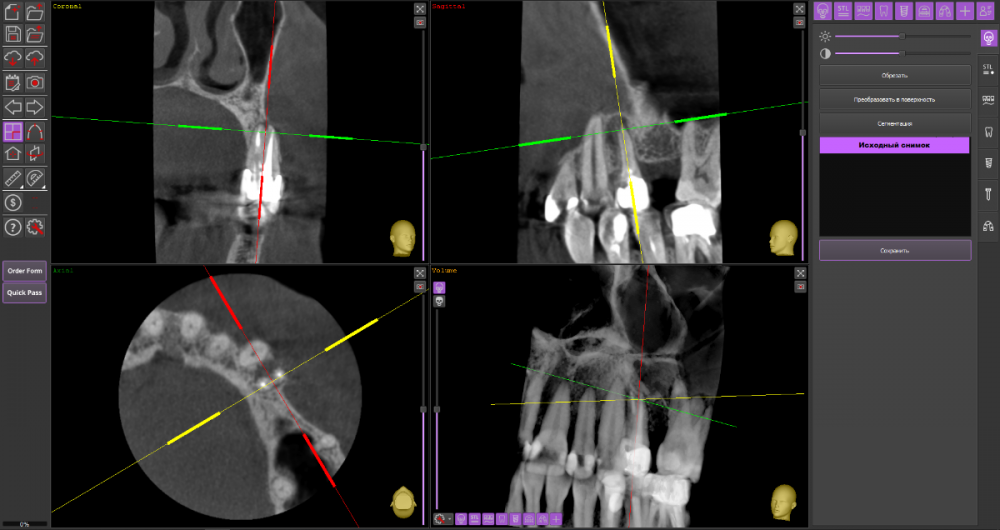

Ulitka Опубликовано 24 января, 2024 Поделиться Опубликовано 24 января, 2024 Добрый день. Уточните, пожалуйста, можно ли спасти зуб 24? Дня 4 назад появилась болезненность при надкусывании, сейчас боли нет ,но есть небольшая припухлость в области корня зуба. Один стоматолог сказал без 3Д снимка, что можно попробовать пролечить и заново протезировать. Второй по 3Д говорит, что у корня зуба нет частично кости, необходимо удалить зуб, чтобы прошло воспаление и кость восстановилась, далее имплантация. Прилагаю КТ https://drive.google.com/file/d/1xQxirzscf1404qjDOck7pBpt04szT7sa/view?usp=drive_link Ссылка на комментарий

wladdX Опубликовано 25 января, 2024 Поделиться Опубликовано 25 января, 2024 Пара скриншотов 1 Ссылка на комментарий